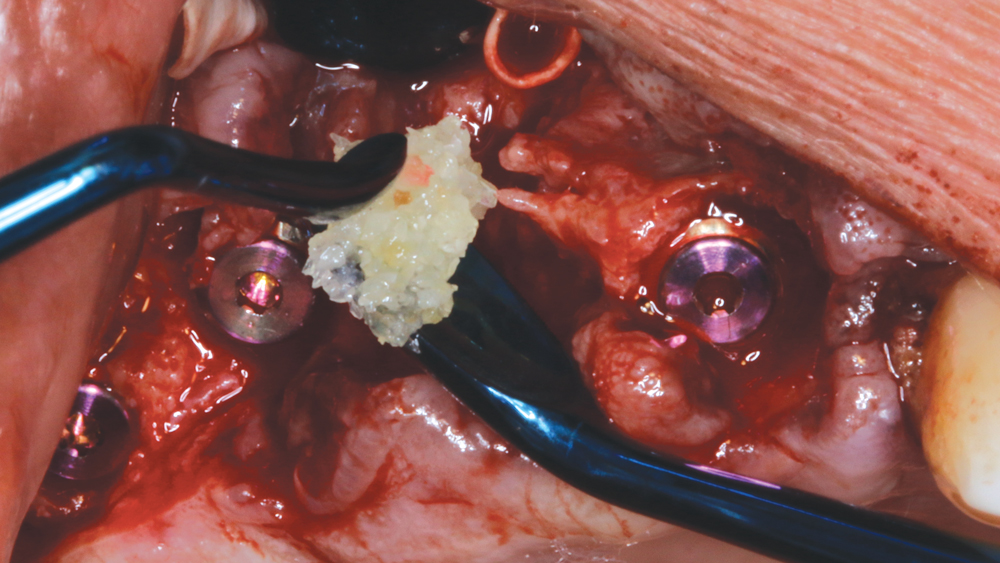

After removing the untreatable teeth, I placed five Hahn Tapered Implants into the extraction sockets, grafted the area with Newport Biologics™ Mineralized Cortico/Cancellous Allograft Blend (Glidewell Direct) mixed with harvested autograft from the osteotomy sites, and used a Newport Biologics Resorbable Collagen Membrane 3-4 (Glidewell Direct) as a barrier against epithelial downgrowth during the healing and remodeling phase.